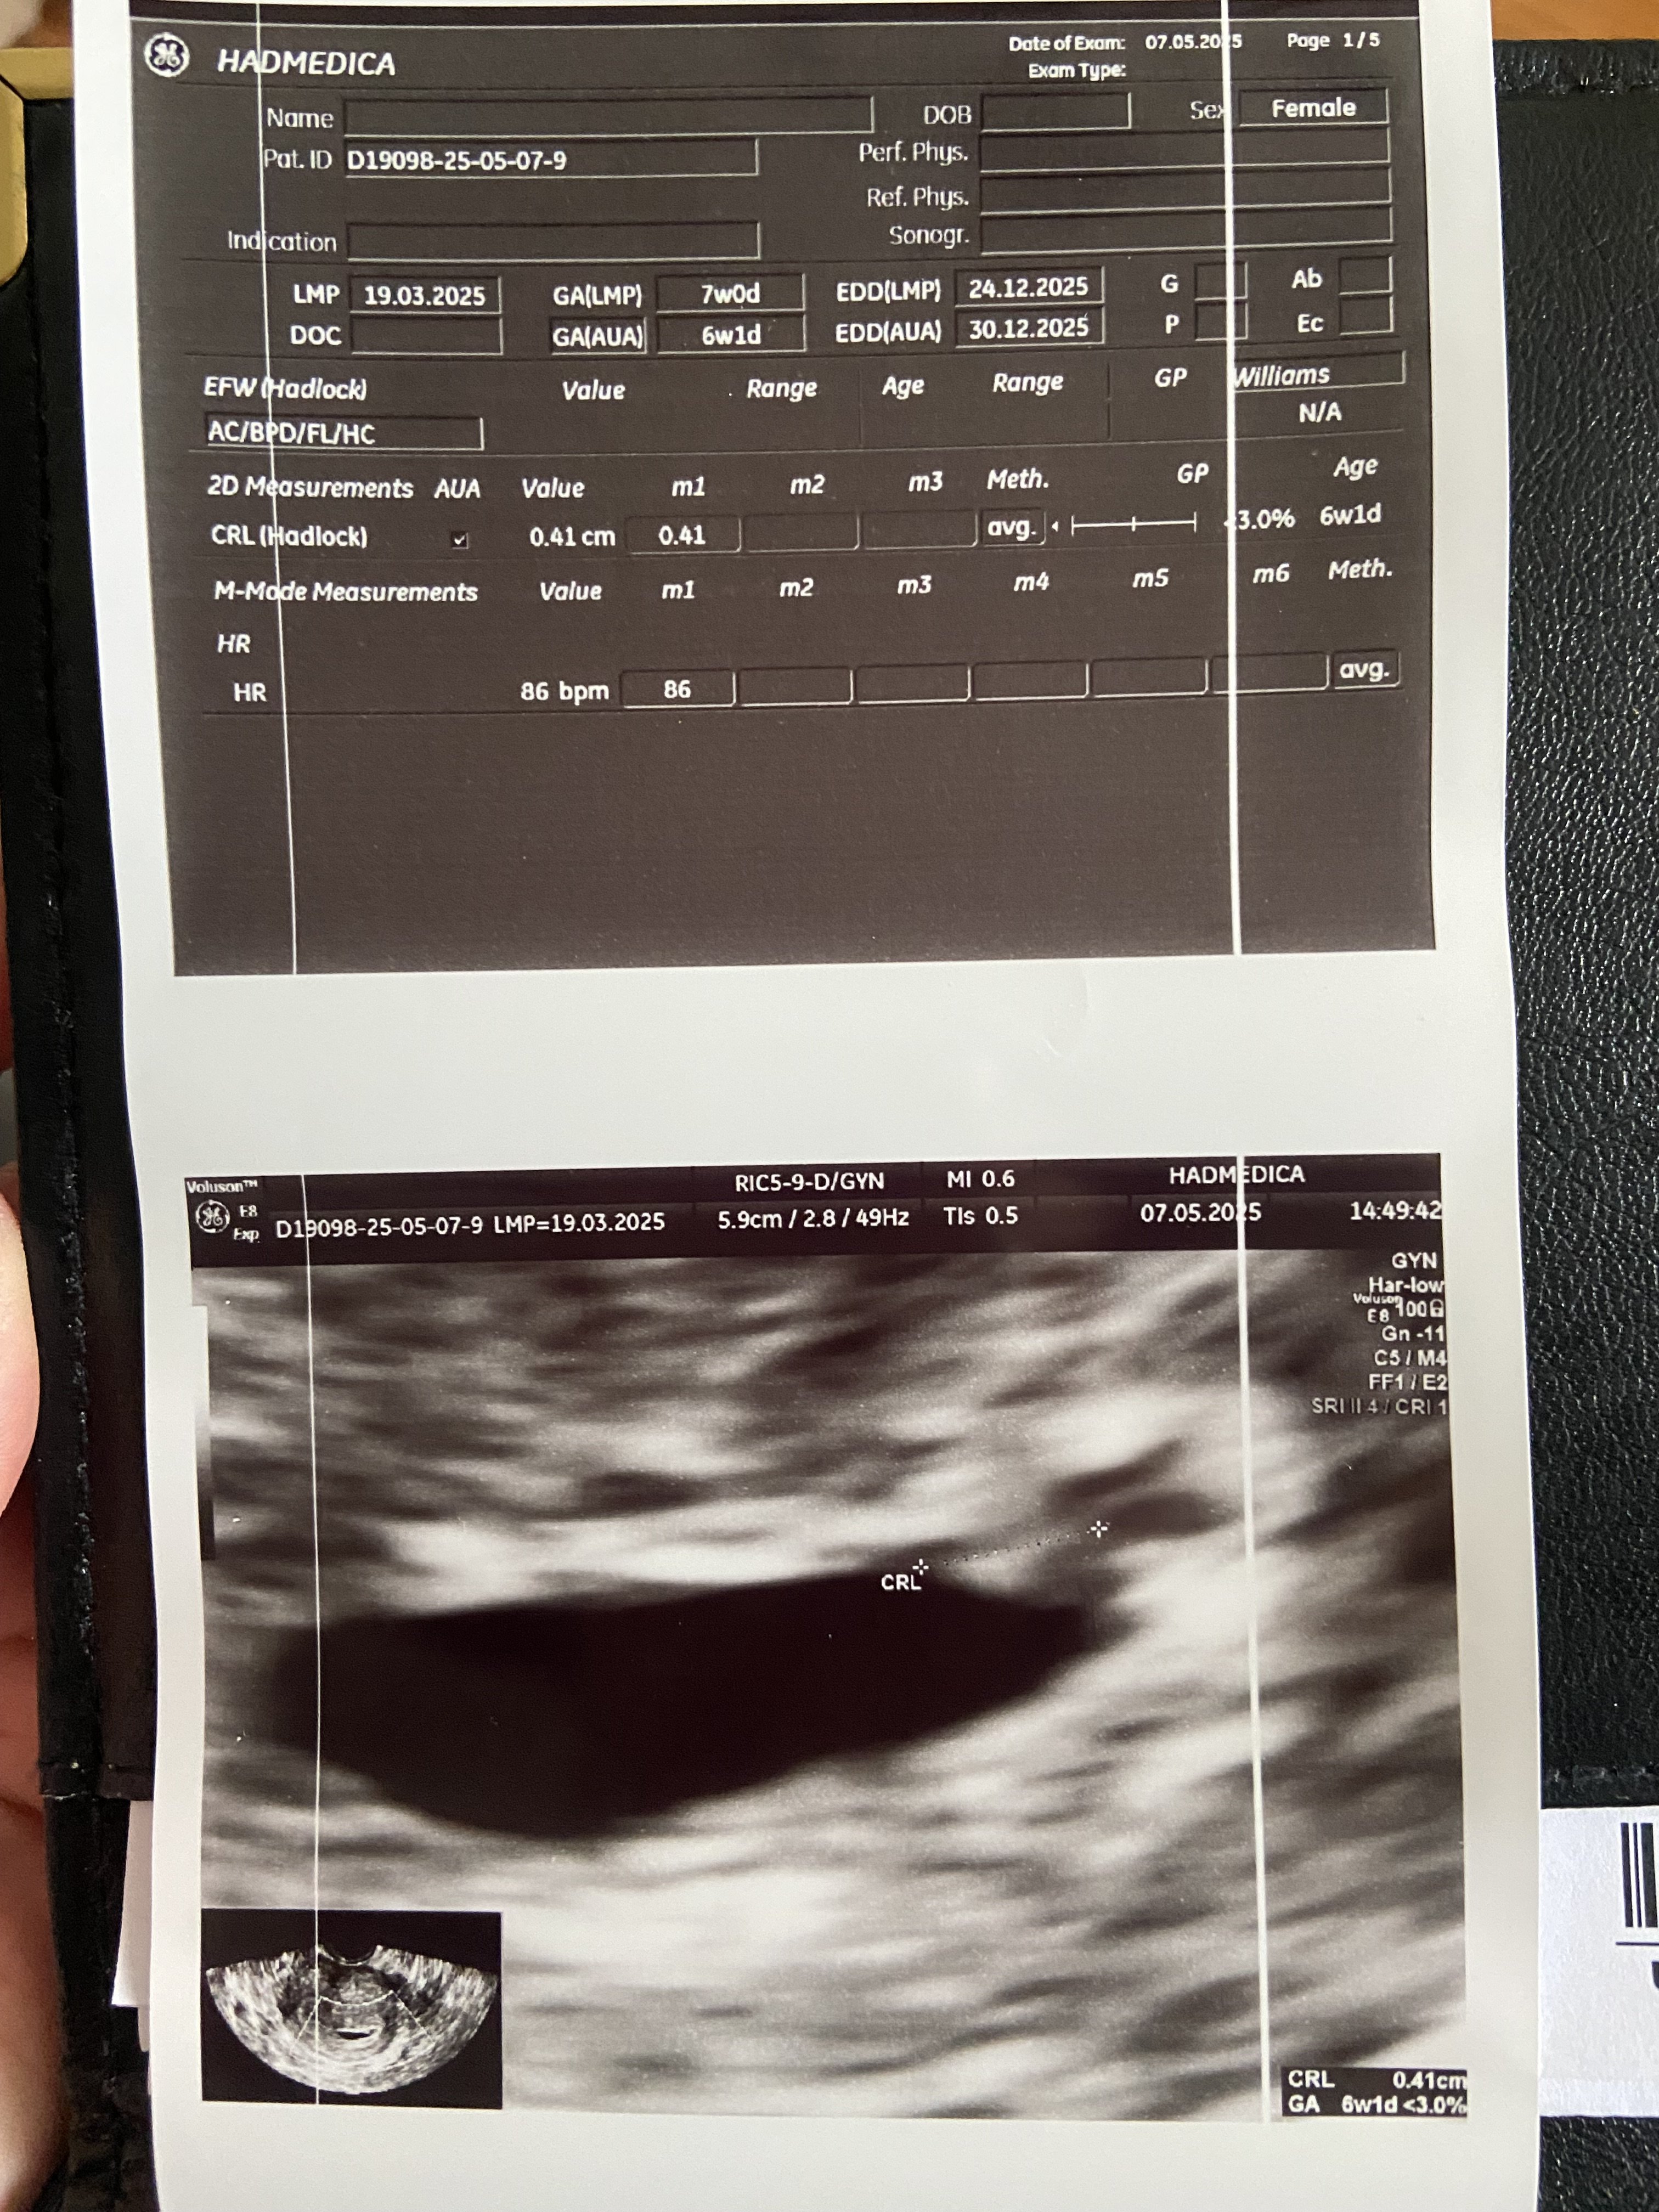

Ja już po wizycie i w pierwszej chwili strach bo pan doktor mówi że nie ma dla mnie dobrych wieści…a za chwilę widzi maleńkie schowane tak że prawie niewidoczne bijące serduszko bpm 86 maleńkie ale szalone bo to dopiero 6t1d. Jestem mega szczęśliwa bo widziałam te maleńkie bijące serduszko. Następna wizyta 21.05 i zobaczymy czy będzie nadal wszystko ok. Dziękuję za wsparcie i proszę o więcej bo to dopiero początek naszej historii 😘😘😘😘😘😘😘😘😘😘😘😘😘😘😘😘😘😘